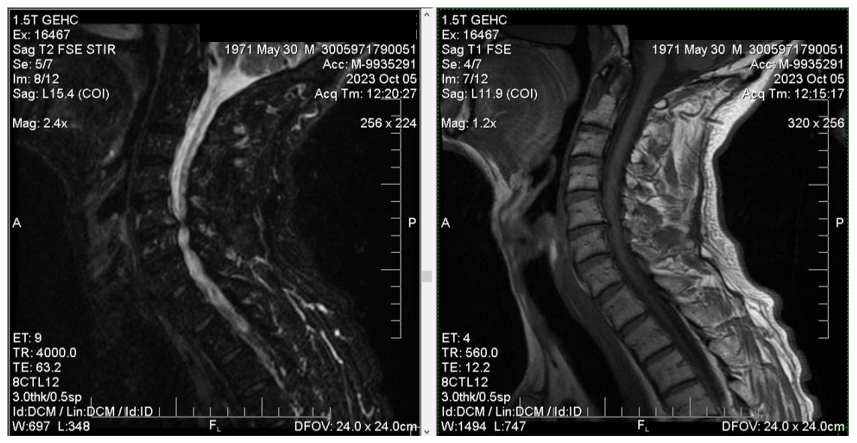

This article covers the case of a 52-year-old male patient. The patient in case was in a car accident (drove a motor vehicle) in which he injured his cervical spine (vertebrae C3/C5). He had been diagnosed with herniated disc in the cervical spine region (vertebrae C5/C6) before his accident (Figure 1). Due to his diagnosis, he had suffered from occasional physical pain and neck stiffness. The crash only caused the physical trauma to the already existing disc herniation, significantly worsening its condition.

Figure 1 MRI scan before the accident showing herniated disc